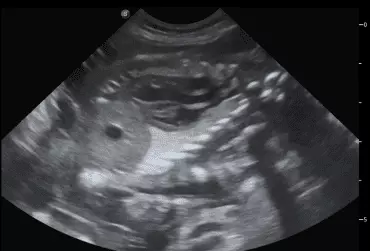

W literaturze opisano niewiele przypadków ciąż bliźniaczych jednokosmówkowych u suk. W trakcie wczesnej diagnostyki ultrasonograficznej ciąży u suki rasy whippet (chart angielski) zobrazowano pęcherz ciążowy, w którym znajdowały się dwa zarodki. Podczas badań kontrol­nych zarodki, a później płody wykazywały prawidłową organogenezę i żywotność. Ich rozwój przebiegał podobnie względem pozostałych ośmiu płodów. W 63. dniu ciąży wykonano zabieg cesarskiego cięcia i wydobyto dwa płody tej samej płci, o bardzo podobnym wyglądzie, z dwóch pęcherzy płodowych przyczepionych do jednego łożyska, oraz pozostałe osiem płodów.

Ryzyko związane z ciążą bliźniaczą jednokosmówkową u ciężarnych suk nadal jest nieznane, istnieją jednak doniesienia o śmierci płodu lub płodów w ciążach jednokosmówkowych u tego gatunku. Badanie ultrasonograficzne w czasie ciąży pozwala na wczesne rozpoznanie ciąży jednokosmówkowej, a monitorowanie żywotności płodów może ograniczyć ryzyko powikłań położniczych i przynieść korzyści zdrowotne zarówno samicy, jak i rodzeństwu z miotu.